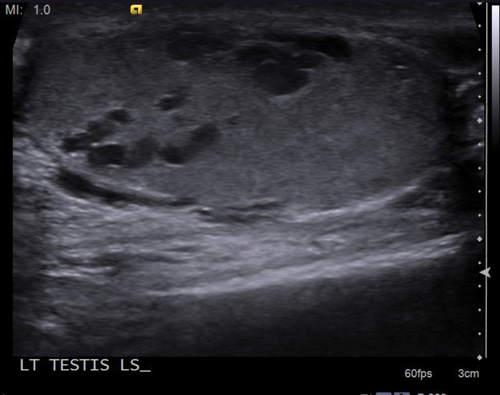

Figure 3: Anechoic, cystic appearing structures seen within the left testis.

Dilated intratesticular veins are seen, which are usually adjacent to the mediastinum testis. On grey-scale ultrasound, this will appear as an anechoic tubular structure, which may have a similar appearance to an intratesticular cyst or tubular ectasia (Figure 3) and it is imperative to apply Doppler ultrasound in order to assess for vascularity (Figure 4). The flow within the varicocele will again be shown to increase and demonstrate reversal of flow when Valsalva manoeuvre is applied (Figure 5).